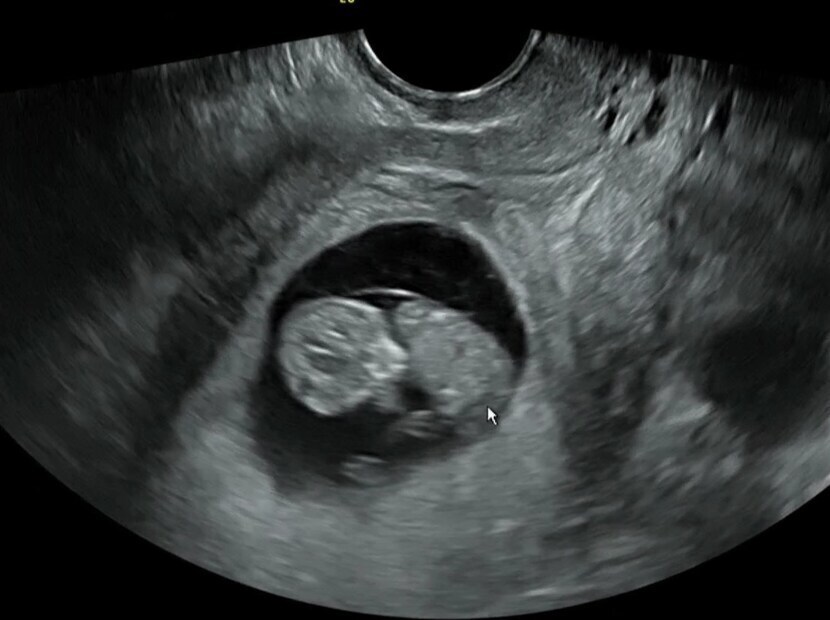

10주차 대박복권~♡

8년만에 둘에서 셋이 됐어요.♡